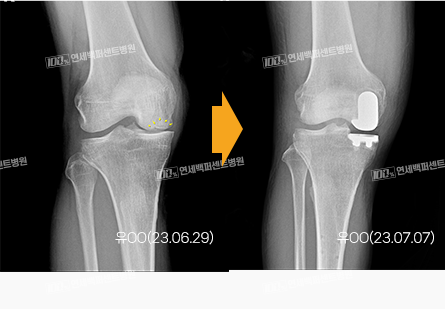

손상된 부분만 선택적으로,

부분 치환술(반치환술)

로봇으로 가능

풍부한 수술 노하우로,

수술 상처 최소화